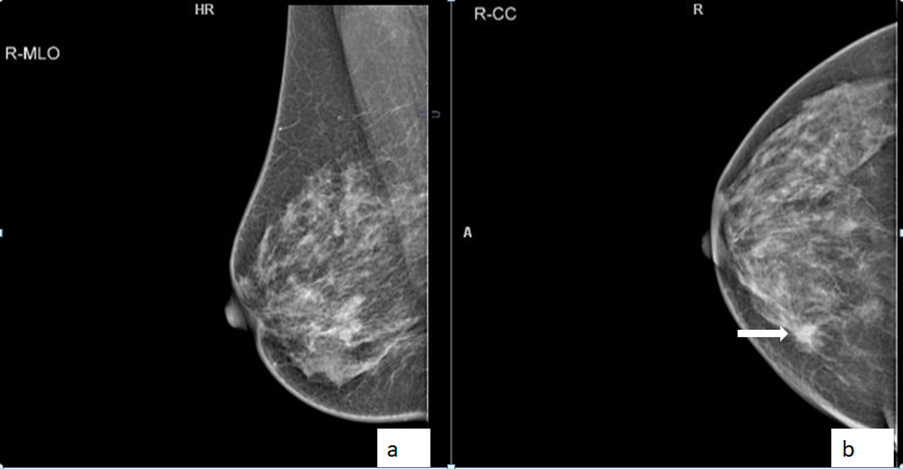

A 33-year-old lady presented with a painless palpable lump in left bre...

Read More